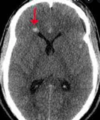

Signo de la cuerda ( ictus ACM ) HIPERAGUDO